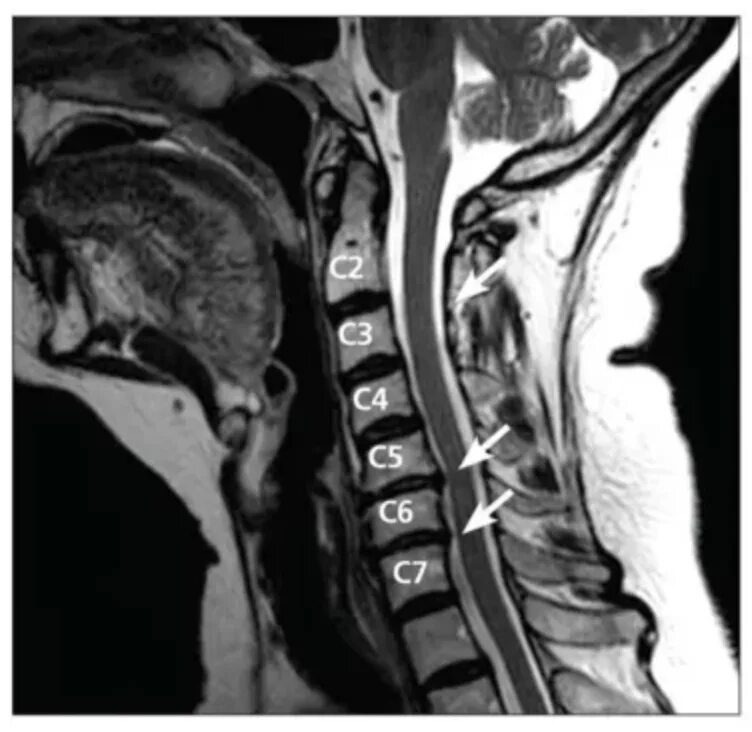

Грыжи дисков с3 с7